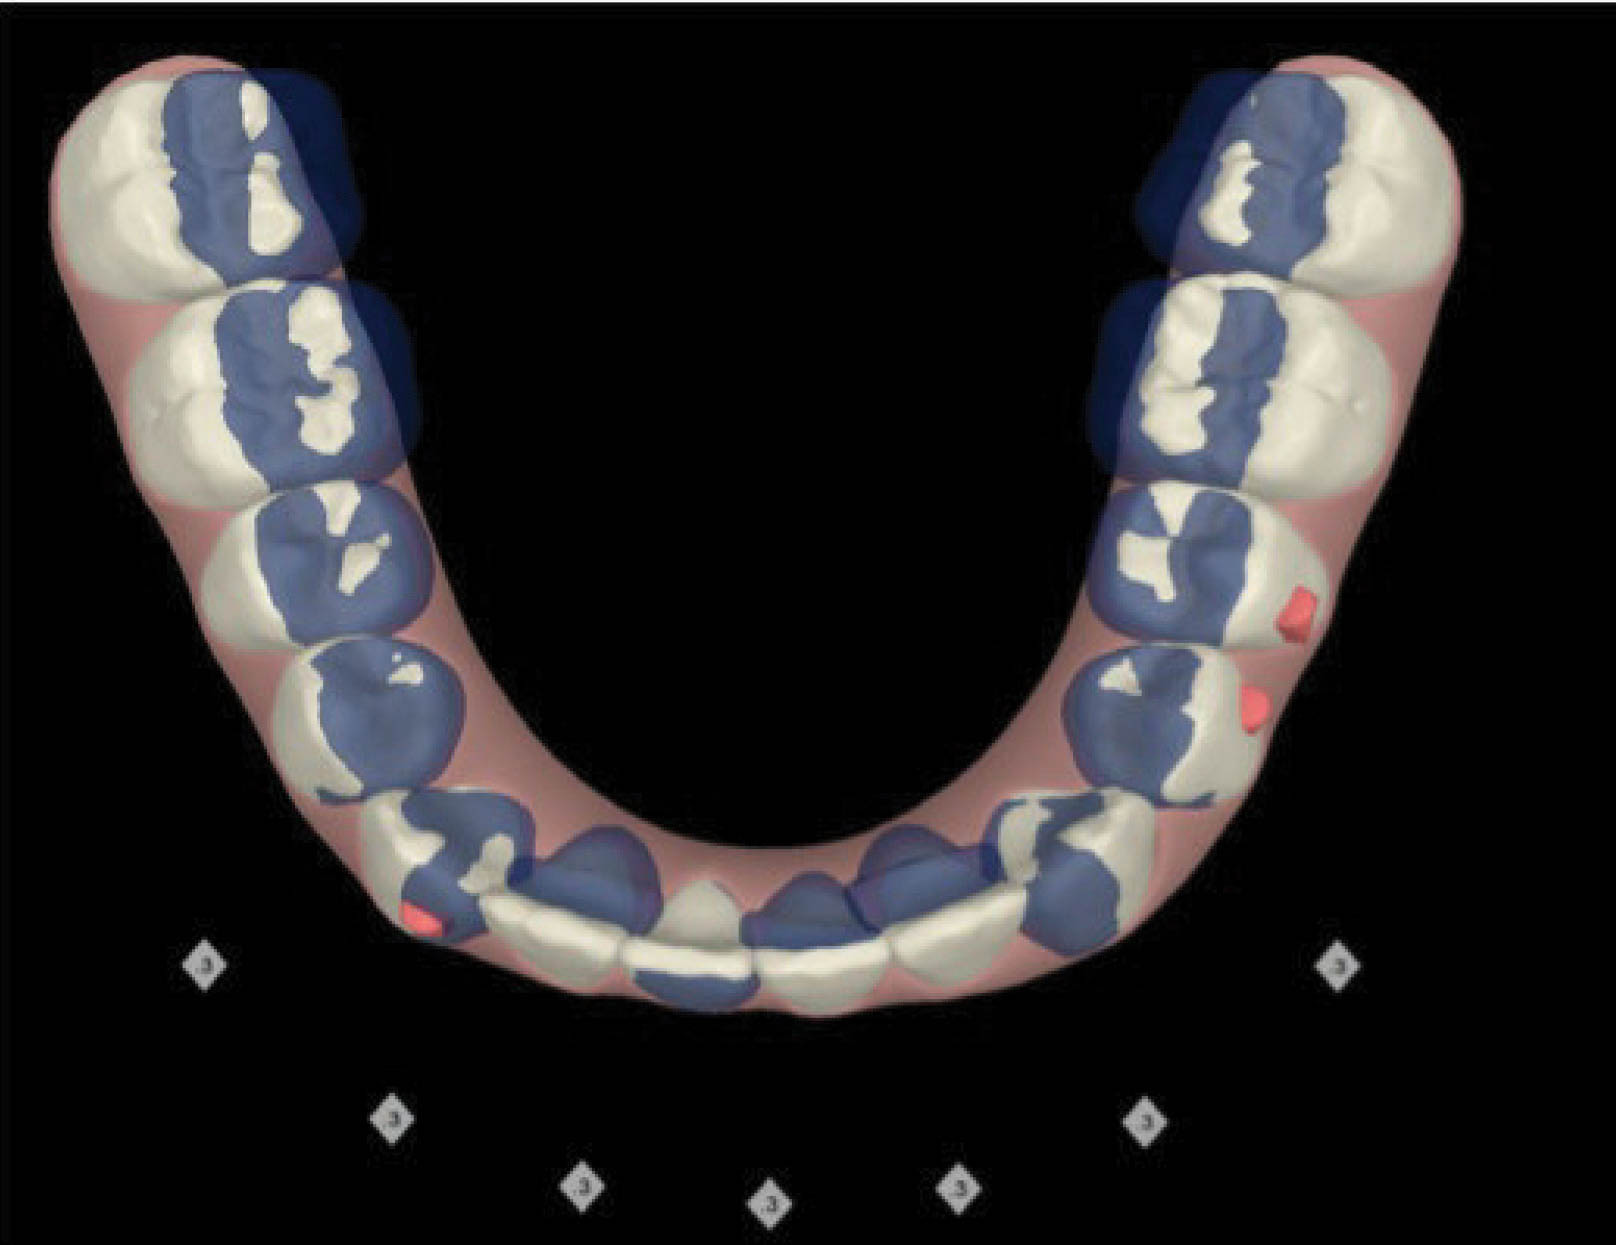

شکل 145-6 نحوه مرتب شدن دندانهای قدام پایین با 0.3mm استریپ هر کنتاکت را نشان میدهد. در پایان درمان قوس پایین کاملاً صاف شده است (شکل 146-6).

شکل 145-6